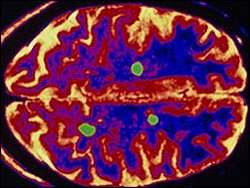

Essa é uma doença rara, causada pelo rápido encurtamento de longas sequências repetitivas de DNA que ficam na extremidade dos cromossomos (os telômeros) - para estudar suas células-tronco.

Em função disso, os telômeros das células de pacientes com disqueratose congênita vão se encurtando progressivamente em cada divisão celular até chegar a um ponto de crise cromossômica em que a célula para de se dividir (entra em senescência), morre ou gera instabilidade genética, o que pode induzir ao câncer e ao envelhecimento celular.